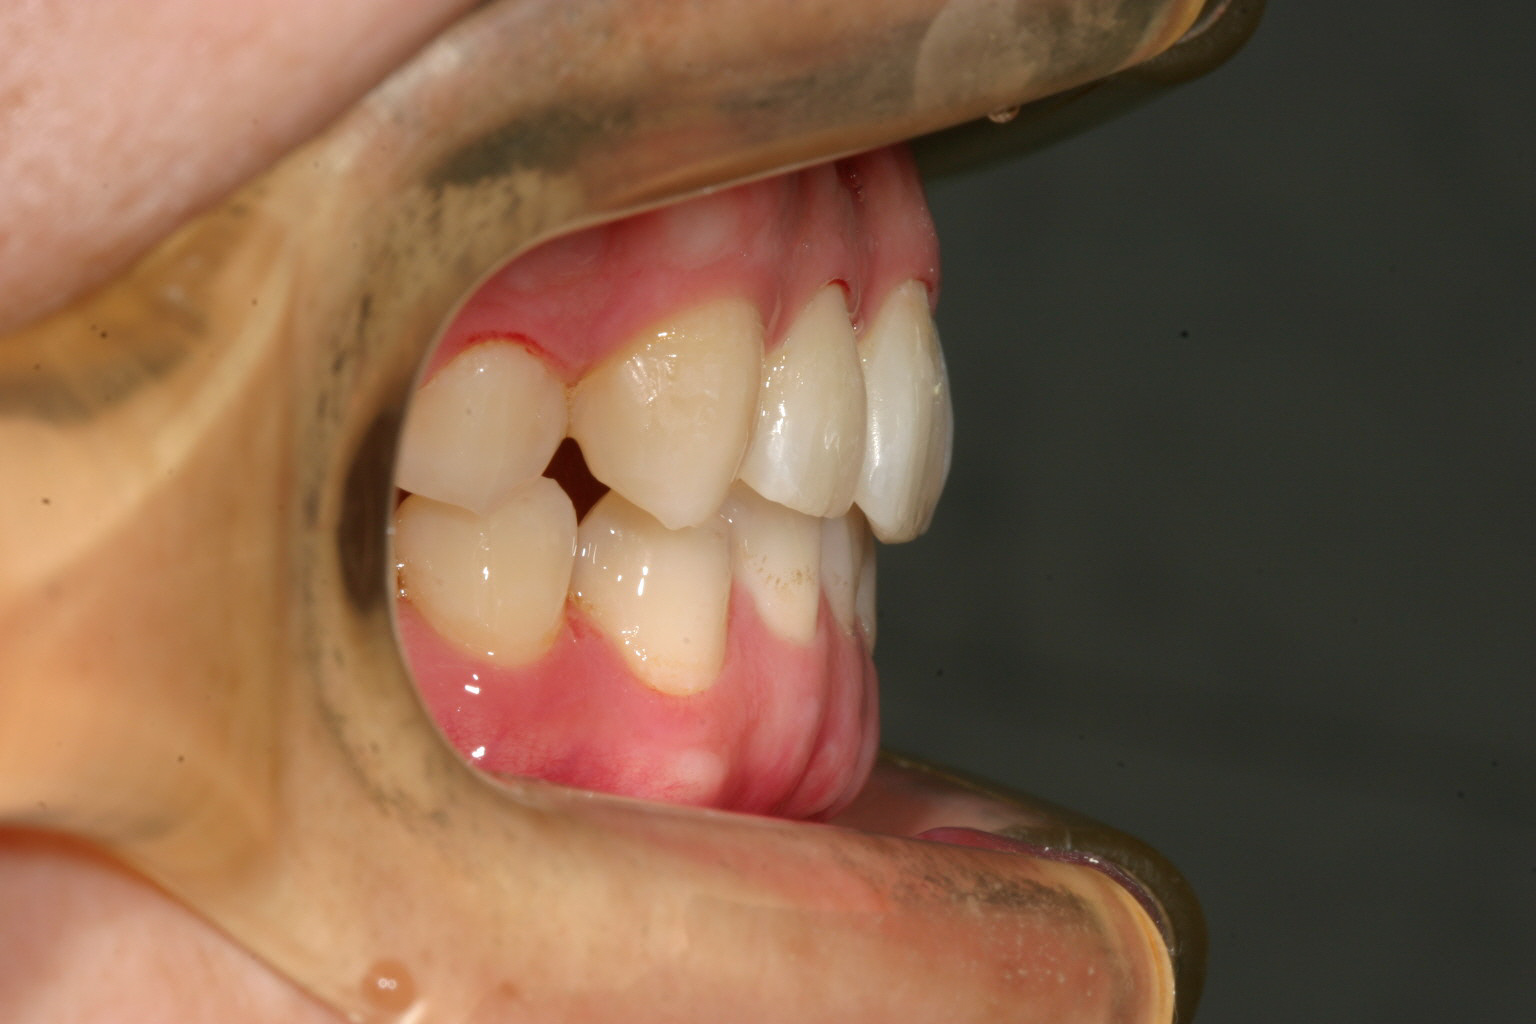

こう言った場合まず上下顎のアーチを広げるとともに、下顎の臼歯の傾斜も立て直す事により咬合高径も上がり結果として叢生も取れ上下前歯のガタつきも改善しました。

インビザラインと言う装置は咬み合わせの深いケースを浅くするのが結構苦手な装置で難儀する事が多いのですが、今回の様に下顎臼歯を立てる事により噛み合わせが浅くなってくれましたので、ホッとしました。笑

今回は患者様が一生懸命頑張って頂いたお陰で難なく治療が終了したと言う感じです。

この程度の治療でしたら一年余りでこれくらいまで治療できると言ういい症例です。

このケースもかなり古い症例ですから1年2ヵ月もかかりましたが、今だと加速矯正装置を使用してもらいますから半年もかからずに終了すると思います。